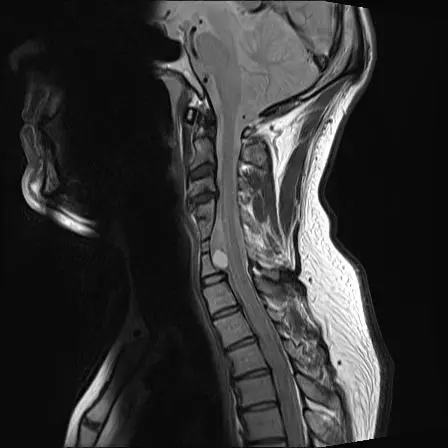

This is my neck. I was born with this and it was discovered when I was 41. There are fused vertebrae from C4-C7, malformed discs, deformed vertebrae, a bulging disc touching my spinal cord and the dermoid tumour on my spinal cord.